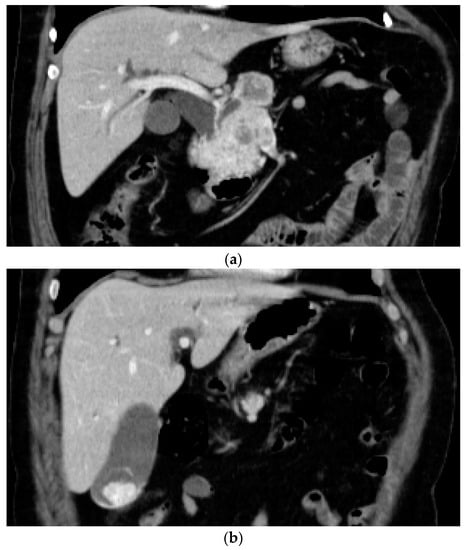

A 61-year-old male presented to the gastroenterology department with involuntary weight loss and upper abdominal pain. The patient was suffering from hypertension and type 2 diabetes mellitus, for which he was taking calcium channel blockers, an angiotensin receptor blocker and insulin. He had undergone left nephrectomy for RCC 6 years previously. Physical examination revealed an overweight patient with a postoperative abdominal scar and orthostatic hypotension. Laboratory examinations revealed mild normocytic anemia, elevated HbA1c and a decreased glomerular filtration rate. A CT-scan revealed a 6/5 cm hyperenhancing mass in the head of the pancreas, with consecutive dilatation of the common bile duct, and a 28/18 mm lesion with similar enhancing pattern in the gallbladder (Figure 2a,b), suggestive of metastasis, considering the RCC history. EUS-FNB of the pancreatic mass confirmed the diagnosis of RCC metastasis. Cholecystectomy and treatment with tyrosine kinase inhibitors were recommended.

Figure 2.

(a) Contrast-enhanced computed-tomography scan showing hyperenhancing mass in the head of the pancreas, with consecutive common bile duct dilation. (b) Contrast-enhanced computed-tomography scan showing hyperenhancing mass in the fundus of the gallbladder.